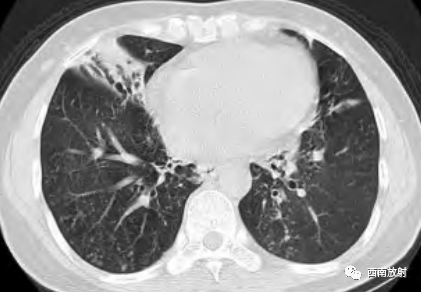

▲图:56岁女性,支气管扩张型非结核分枝杆菌感染患者,侧位胸片显示不均匀的网状影以及中叶和舌段体积缩小。横轴位平扫CT显示广泛的支气管扩张及中叶和舌段体积缩小、多发细胞性细支气管炎、黏液栓,以及马赛克密度。(病例来自《肺部高分辨率CT》译者:赵绍宏 聂永康)

▲图:冠状位平扫CT显示下叶蜂窝影(来自肺纤维化),以及左肺上叶大的空洞。纤维空洞型非结核分枝杆菌感染通常见于肺气肿,以及右肺下叶小空洞。小空洞在胸上可很难辨认,可能由是同时存在的肺疾病。(病例来自《肺部高分辨率CT》译者:赵绍宏 聂永康)